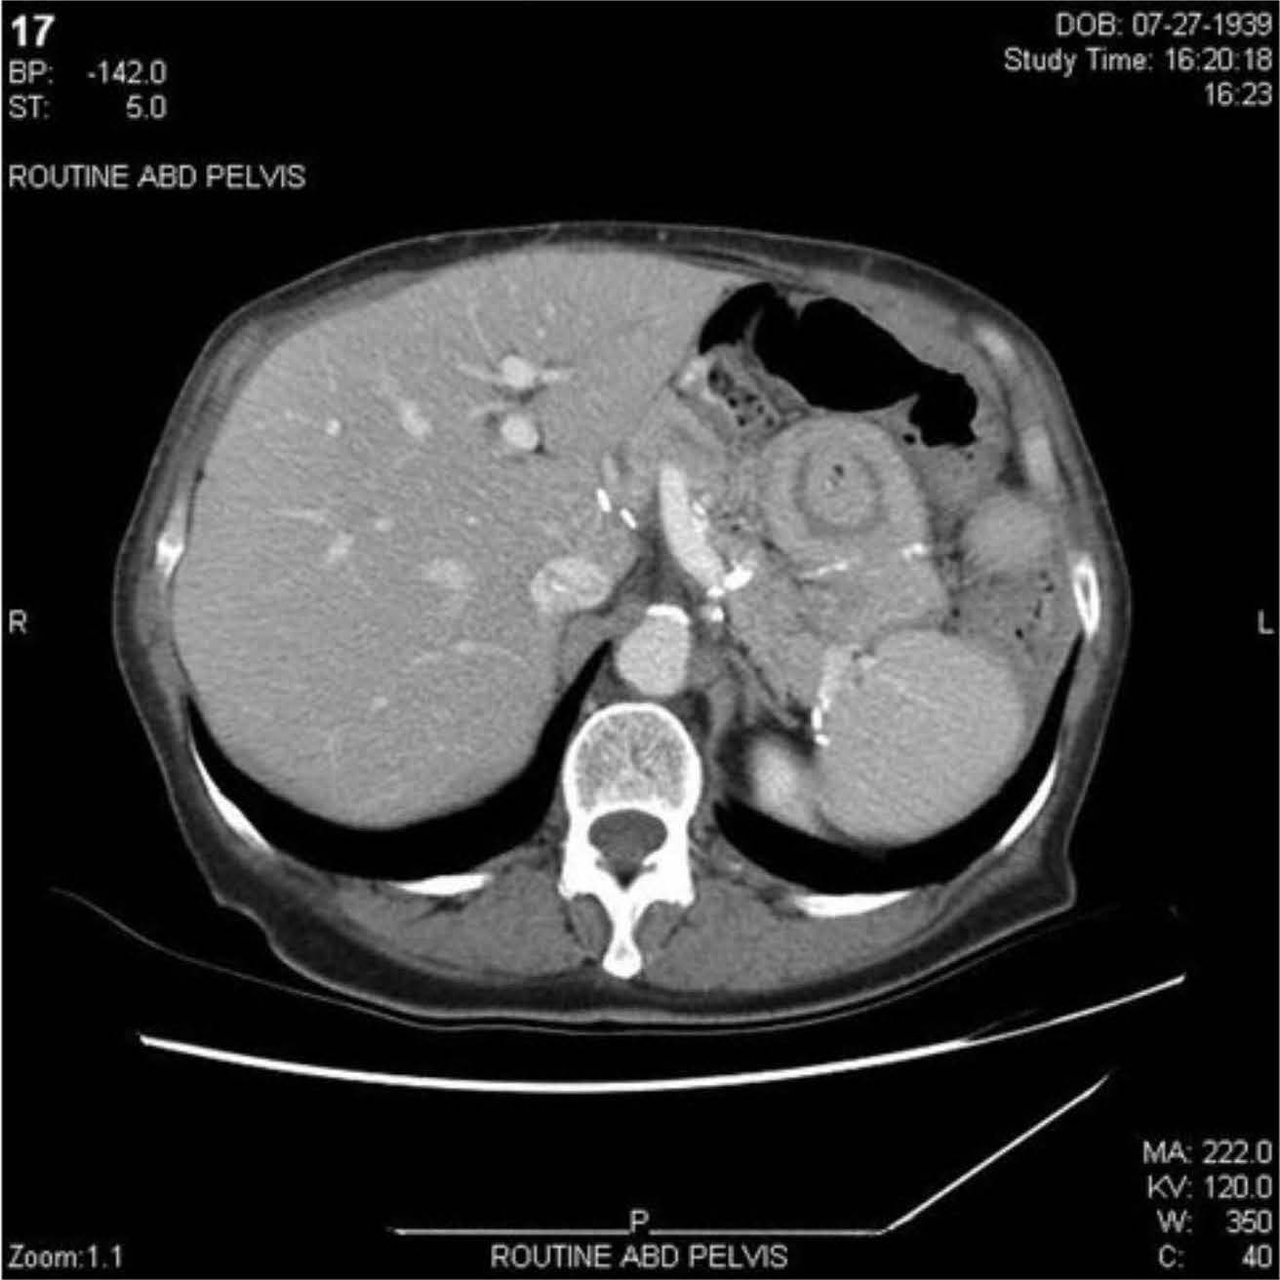

Imaging example: what scans are shown for extent evaluation (illustration)?

After Hodgkin lymphoma confirmation by node biopsy: next best staging test?